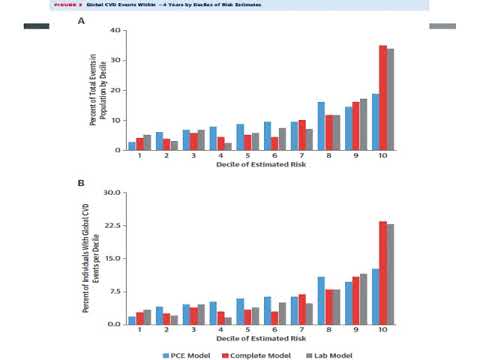

Predictores a corto termino de enfermedad cardiovascular en adultos mayores. Dr. Gerardo Albarracín. Residencia de Cardiología. Hospital C. Argerich. Buenos Aires

Modelos de riesgo basados en biomarcadores. Residencia de Cardiología. Hospital C. Argerich. Buenos Aires